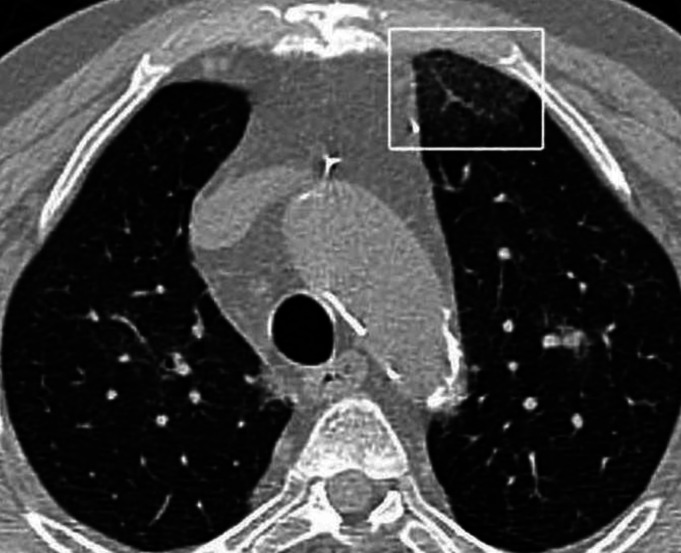

The aim was to compare the computed tomography (CT) semi-quantitative severity scoring (CT-SS) system assessments of COVID-19 pneumonia on initial and follow-up examinations according to the presence of comorbidities. Of the 278 real-time reverse transcription-polymerase chain reaction positive patients, 108 with a follow-up CT scan were evaluated. Then, all CT images were independently reviewed for CT-SS analysis by two reviewers. Reviewers were unaware of the patient laboratory and clinical findings. A quarter of patients had negative findings on their initial CTs. Sixty-one (56.4%) patients showed progression. Disease progression was more frequently observed in patients with type 2 diabetes mellitus (DM) and malignancies (p=0.044 and p=0.019, respectively). Follow-up CTs of patients with comorbidities, especially those with cardiovascular disease (56.4%) and type 2 DM (70.0%), demonstrated an increased frequency of diffuse involvement. The white lung sign was more frequently observed in patients with malignancies (60.0%). In this study, COVID-19 patients with comorbidity showed a higher rate of disease progression than those without comorbidity. Patients with comorbidities more frequently had severe CT findings with high CT-SS. These findings may serve as a guide in the COVID-19 pneumonia follow-up and treatment.